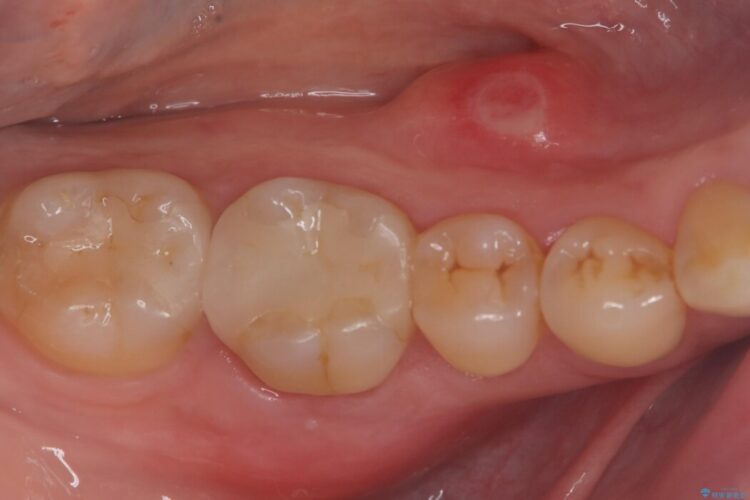

治療では、マイクロスコープで根の中を大きく拡大し、非常に細くなっていた神経の通り道を慎重に見つけ出しました。

次に、根のカーブに沿ってしなやかに曲がるニッケルチタンファイルを使い、根の先まで徹底的に洗浄・殺菌を行いました。汚れを完全に取り除いた後、隙間なくお薬を詰めて密閉しています。

術後の経過は非常に良く、あんなに大きかった膿の袋は消え、健康な骨が再生しているのが確認できました。痛みや腫れも消えて抜歯を免れ、現在は被せ物を入れてしっかりお食事を楽しんでいただけるようになっています。